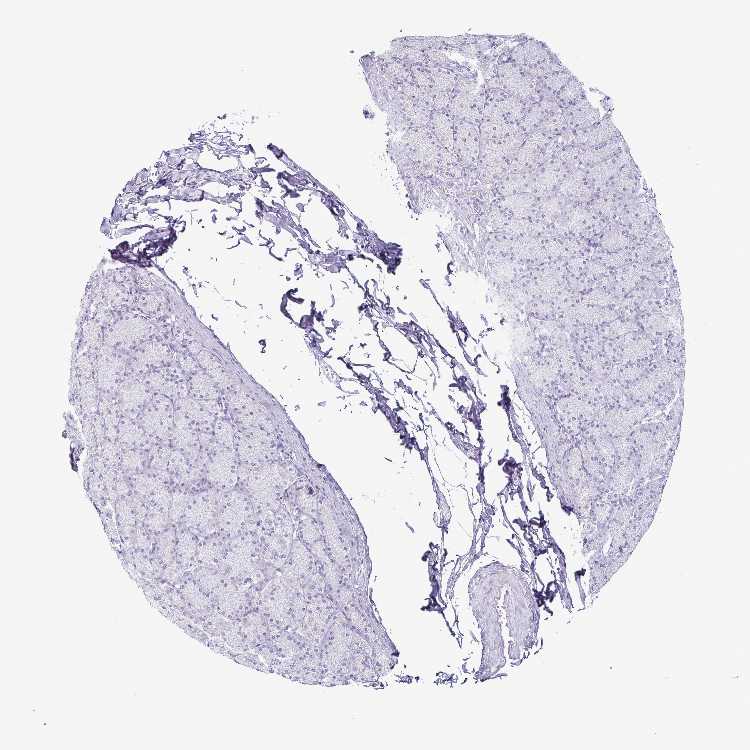

STOMACH 1 - Antibody stainingi

Antibody staining in the annotated cell types in the current human tissue is reported as not detected, low, medium, or high, based on conventional immunohistochemistry profiling in selected tissues. This score is based on the combination of the staining intensity and fraction of stained cells.

Each image is clickable and will lead to virtual microscopy that enables deeper exploration of all samples and also displays staining intensity scores, fraction scores and subcellular localization as well as patient and tissue information for each sample.

Antibody HPA039724

Glandular cells Not detected